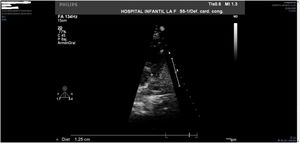

Sin embargo, en la revisión posterior a los siete años de la primera intervención, se objetivó un incremento significativo del gradiente registrado en TSVD (89 mmHg) atribuible a un componente mixto muscular subvalvular y valvular con un anillo pulmonar de 12,5 mm (z-score = -3,4) (figs. 1 y 2). El estudio preoperatorio se completó con una cardio-resonancia magnética nuclear (RMN), que además de confirmar los hallazgos ecocardiográficos nos ayudó a clarificar que el componente muscular subvalvular detectado ecocardiográficamente correspondía a un rodete fibromuscular prácticamente pegado al plano anular inferior de la válvula pulmonar (figs. 3 y 4).

El último control clínico-ecocardiográfico ambulatorio disponible muestra una paciente asintomática con estenosis pulmonar valvular leve (gradiente 23 mmHg) con anillo pulmonar de 21 mm (z = + 0,02) e insuficiencia valvular leve (figs. 5 y 6).